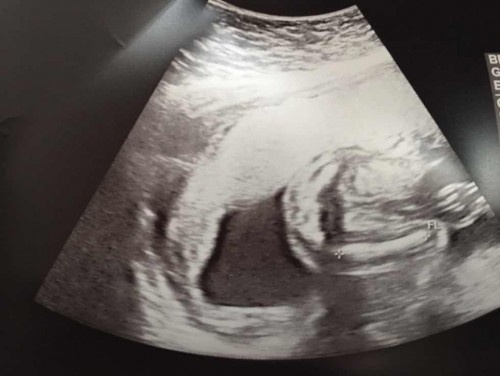

ยังไม่ทราบเพศ🤰🏻

น้ำหนักลูกตามเกณฑ์แต่น้ำหนักแม่เพิ่มมา4โล 👼🏻